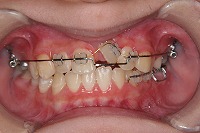

10歳4か月 | 10歳10か月 | 11歳1か月 | 11歳3ヵ月 | 11歳4か月 | 11歳7か月 | 11歳8か月 | |

反対咬合と前歯が生えてこない事を主訴に来院された、10歳4か月の男の子です。診断「下顎骨の過成長による骨格性反対咬合で上顎正中の左方偏位と埋伏歯を伴う」1期治療で反対咬合の解消と埋まっていた前歯を牽引しました。